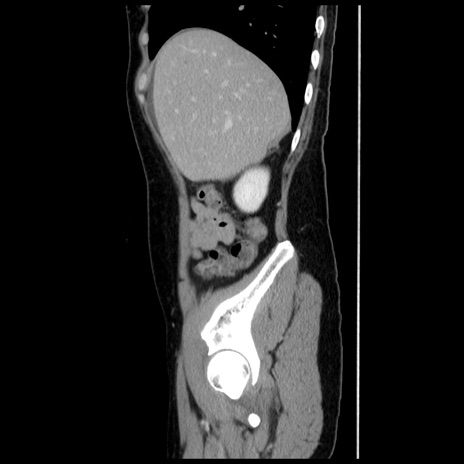

症例10(矢状断像)

【症例】 50歳代女性

【主訴】 腹痛

【現病歴】前日生レバーを食べた。今朝に排便あり。 昼前に突然発症の腹痛を生じ、当院救急外来を受診した。

【既往歴】 子宮筋腫にてで子宮全摘後

【身体所見】 意識清明、腹部:平坦、軟、下腹部やや左を中心に圧痛・反跳痛あり、筋性防御あり

【データ】WBC 7800、CRP 0.07